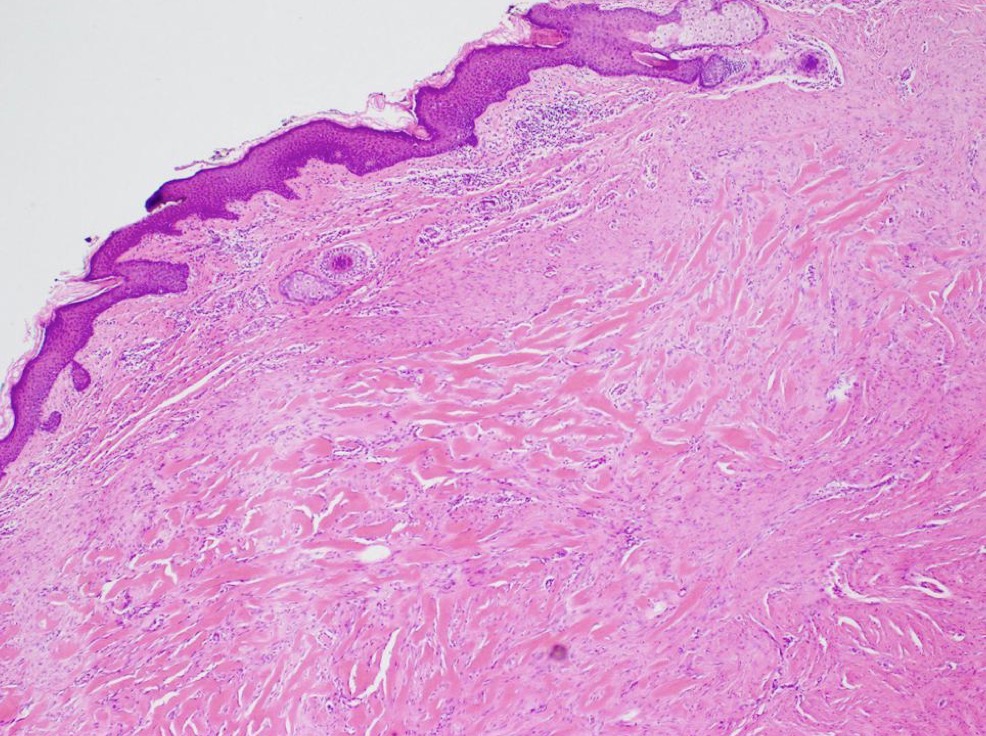

C- identify the marked structure

A- Granulation tissue

B- ingrowth of capillaries filled with RBCs accompanied with fibroblast producing collagen aids in healing of inflammation

C- active fibroblast

A- identify

B- describe

A- Granulation tissue ( healing skin wound )

B- skin surface re-epithelialized , below it there is granulation tissue with capillaries and fibroblast producing collagen . After a month there will be small collagenous scar remain